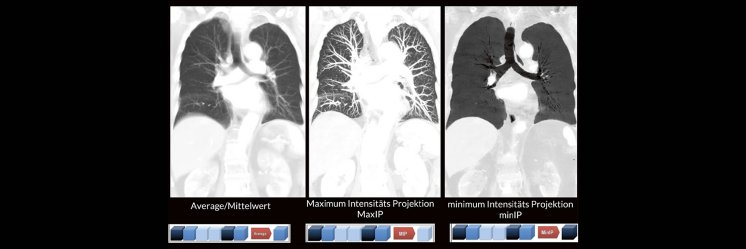

Darüber hinaus werden die unterschiedlichen MPR-Techniken wie z. B. Maximum Intensitäts- Projektionen (MaxIP´s) und minimum Intensitäts Projektionen (minIP´s) oft nicht routinemäßig angewendet. Dabei können verschiedene Pathologien durch den zielgerichteten Einsatz der unterschiedlichen MPR-Techniken oft viel einfacher und besser diagnostiziert werden.

• Maximum Intensität Projektion

• Minimum Intensität Projektion